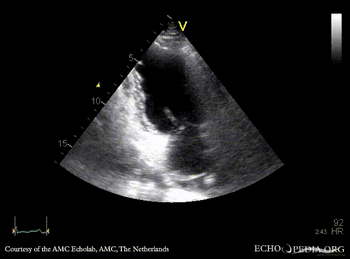

| PSAX: mobile fragment of papillary muscle | A5CH |

| A2CH | A4CH: severe mitral regurgitation, excentric jet |